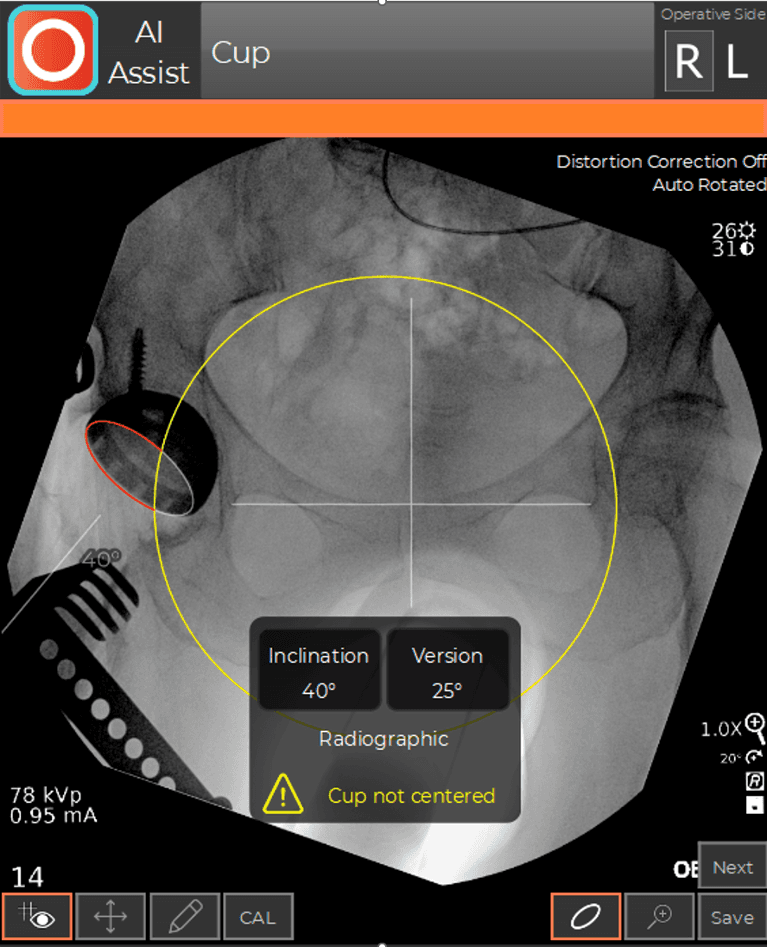

During a hip replacement using the Direct Anterior Approach, the patient is positioned supine on a traction table (the Hana® table) that allows independent positioning of the limbs during surgery. This position facilitates the use of C-arm fluoroscopy. C-arm fluoroscopy is an intra-operative x-ray camera that projects images on a computer monitor in the operating room and is used to navigate the position of the hip socket and stem in real-time during the procedure. The fluoroscopic images are analyzed by computer software (OrthoGrid Systems, Inc.), which registers multiple anatomic landmarks in order to calculate socket position, leg length, and offset. This allows the surgeon to make small adjustments intra-operatively, in order to ensure an anatomic reconstruction.